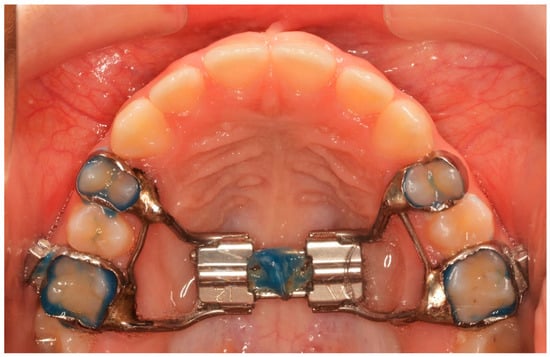

All patients received a Hyrax expander, as the initial part of their treatment, with bands cemented at least on the first maxillary permanent molars and on the first premolars or maxillary deciduous first molars. All Hyrax expanders were manufactured by the same laboratory, and all screws were by the same company. The expansion screw was activated twice a day (0.25 mm per turn, 0.5 mm daily) until the palatal cusp of the maxillary first molar occludes with the buccal cusp of the mandibular first molar. At the end of expansion, the Hyrax screw was stabilized with ligature wire and light-cured composite (Figure 1).

Figure 1.

The end of the active phase of expansion.

The Hyrax screw remained passive during a 6-month retention period after expansion. Until then, neither fixed nor another orthodontic appliance was used. After the passive period, the Hyrax was removed and replaced by a horse-shoe-type transpalatal arch that was used as a retainer, extending to the palatal surface of the incisors (Figure 2). This type of retainer remains in place until all permanent teeth erupt.

Figure 2.

Horse-shoe-type TPA used after T2 time interval.